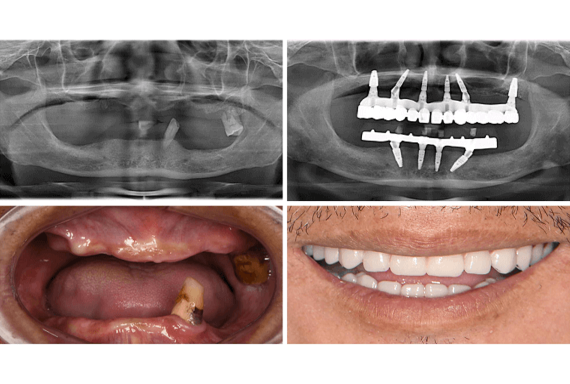

This guide provides a comparative technical analysis of Standard and Advanced full-arch dental implant systems used in edentulous rehabilitation. Pricing for a full mouth of dental implants varies significantly based on equipment class, materials, and procedural precision. The following table outlines key technical specifications influencing cost, performance, and clinical outcomes.